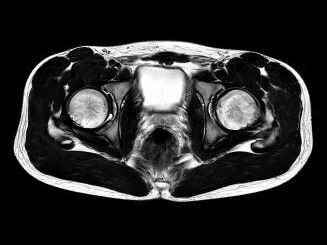

Beispiele von MRT-Becken Aufnahmen